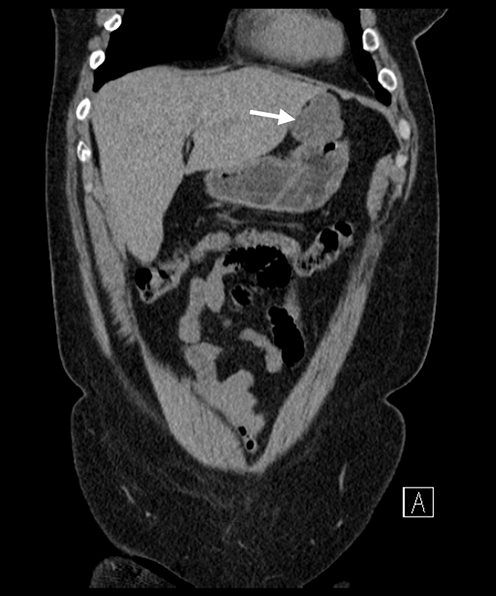

A 62-year-old female with a history of gastroesophageal reflux disease and a 50+ pack year smoking history underwent surveillance chest CT for pulmonary nodules when an incidentally discovered gastric mass was noted. This finding was confirmed with dedicated abdominal and pelvic CT, which demonstrated a 4.1 × 4.3 cm partially exophytic mass on the lesser curvature of the stomach, roughly 9 cm from the gastroesophageal junction (Figure 1). The mass was well circumscribed with no invasion into adjacent structures. Based on the location of the mass and its homogenous appearance on imaging, our initial diagnosis was that of a gastrointestinal stromal tumor (GIST). Apart from the patient’s long-standing reflux disease, she denied any other gastric symptoms.

Figure 1. Dedicated CT Scan of Abdomen and Pelvis After Incidental Discovery of Gastric Mass. Published With Permission